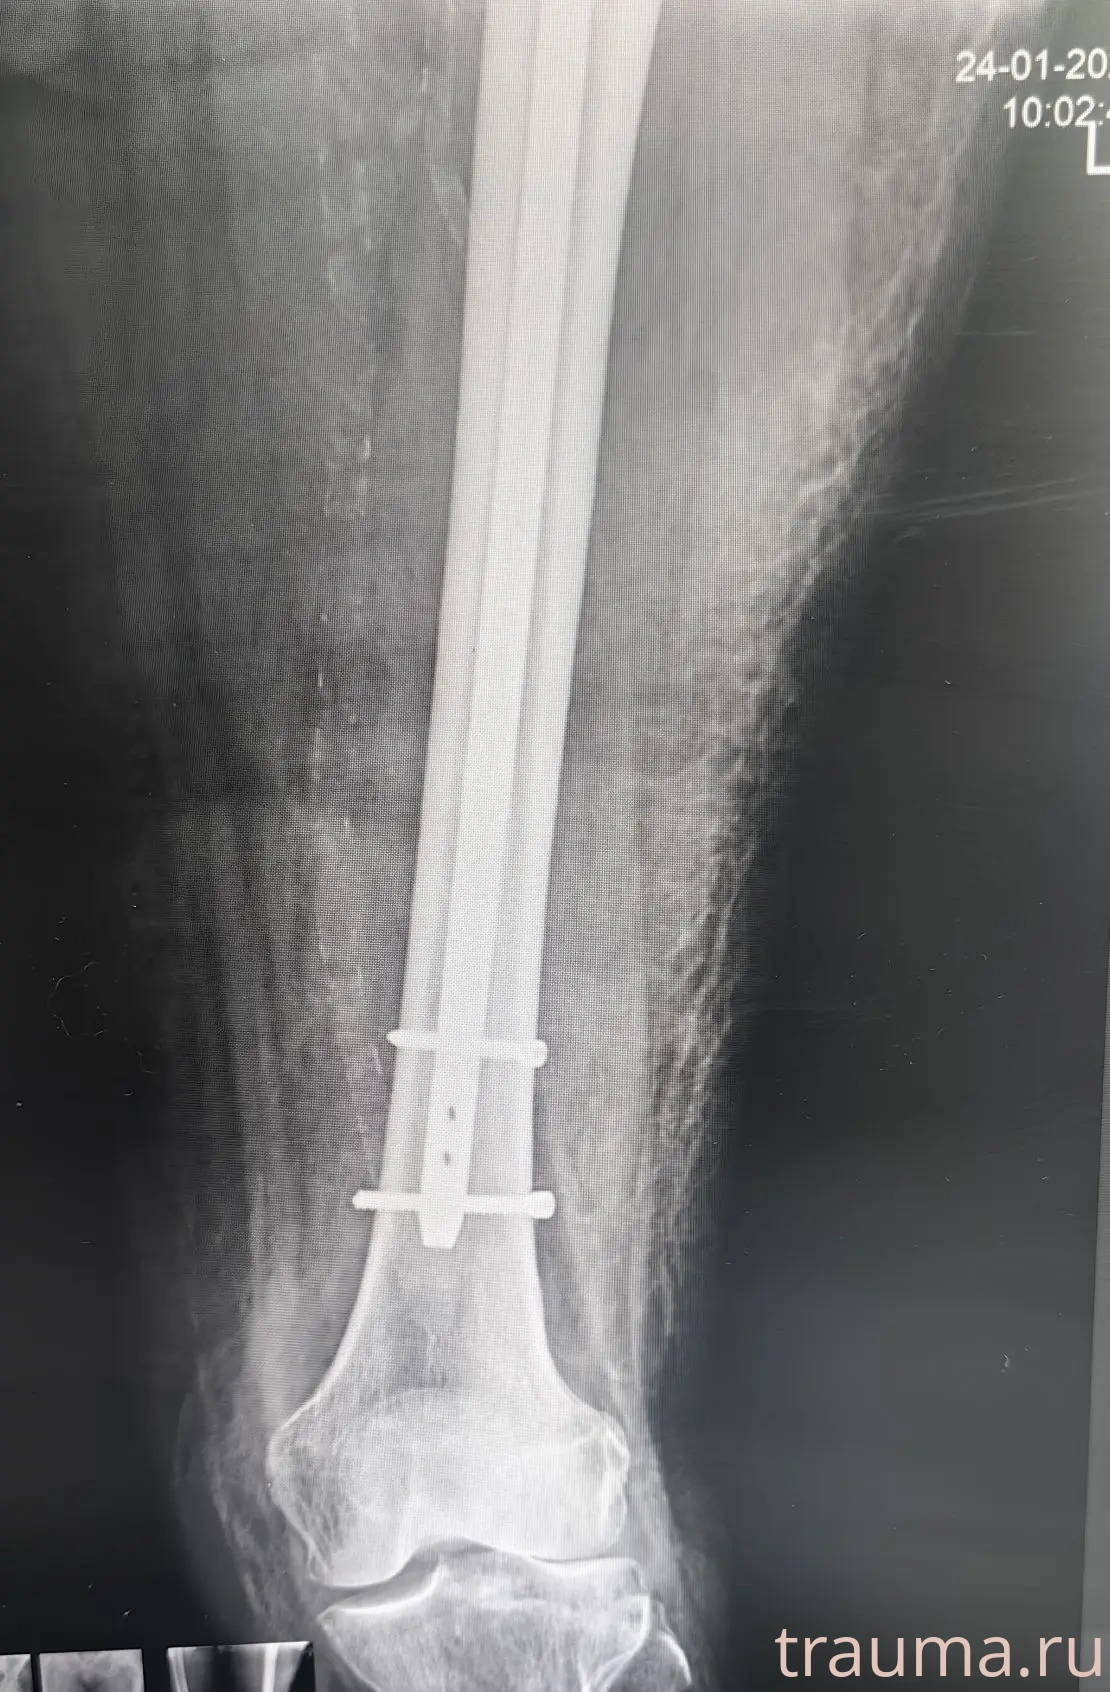

Рентгенограммы

24.01.2026

Рентген на дому: по вашему адресу приезжает врач-рентгенолог, травматолог-ортопед с мобильным рентгеновским аппаратом, проводит диагностику травмы или заболевания, делает необходимые рентгенограммы, дает рекомендации по дальнейшему лечению. Получить качественные снимки в домашних условиях возможно благодаря уникальной методике, разработанной МосРентген Центром для института  Склифосовского